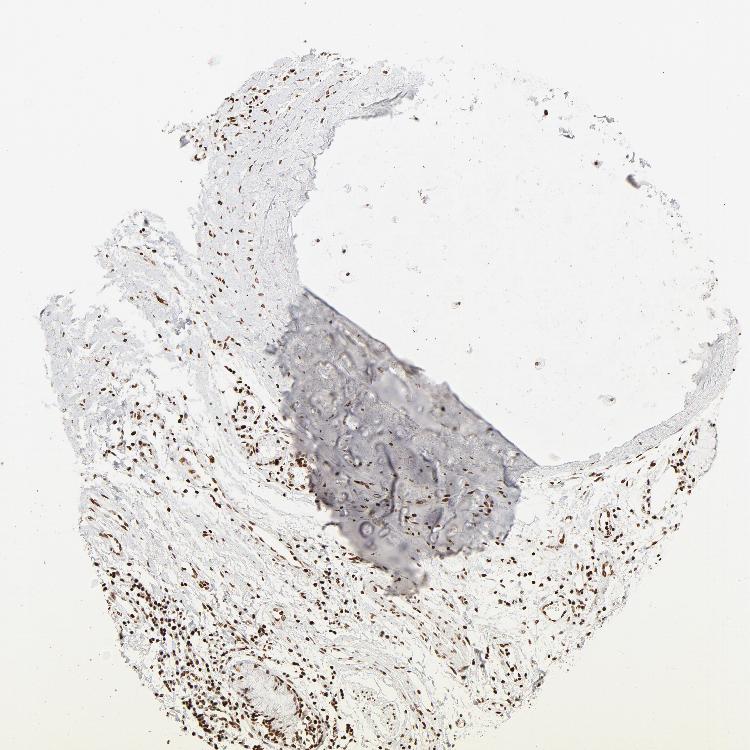

ADIPOSE TISSUE - Antibody stainingi

Antibody staining in the annotated cell types in the current human tissue is reported as not detected, low, medium, or high, based on conventional immunohistochemistry profiling in selected tissues. This score is based on the combination of the staining intensity and fraction of stained cells.

Each image is clickable and will lead to virtual microscopy that enables deeper exploration of all samples and also displays staining intensity scores, fraction scores and subcellular localization as well as patient and tissue information for each sample.

Antibody HPA003506Antibody HPA053314Antibody CAB037206

Adipocytes MediumNot detectedMedium